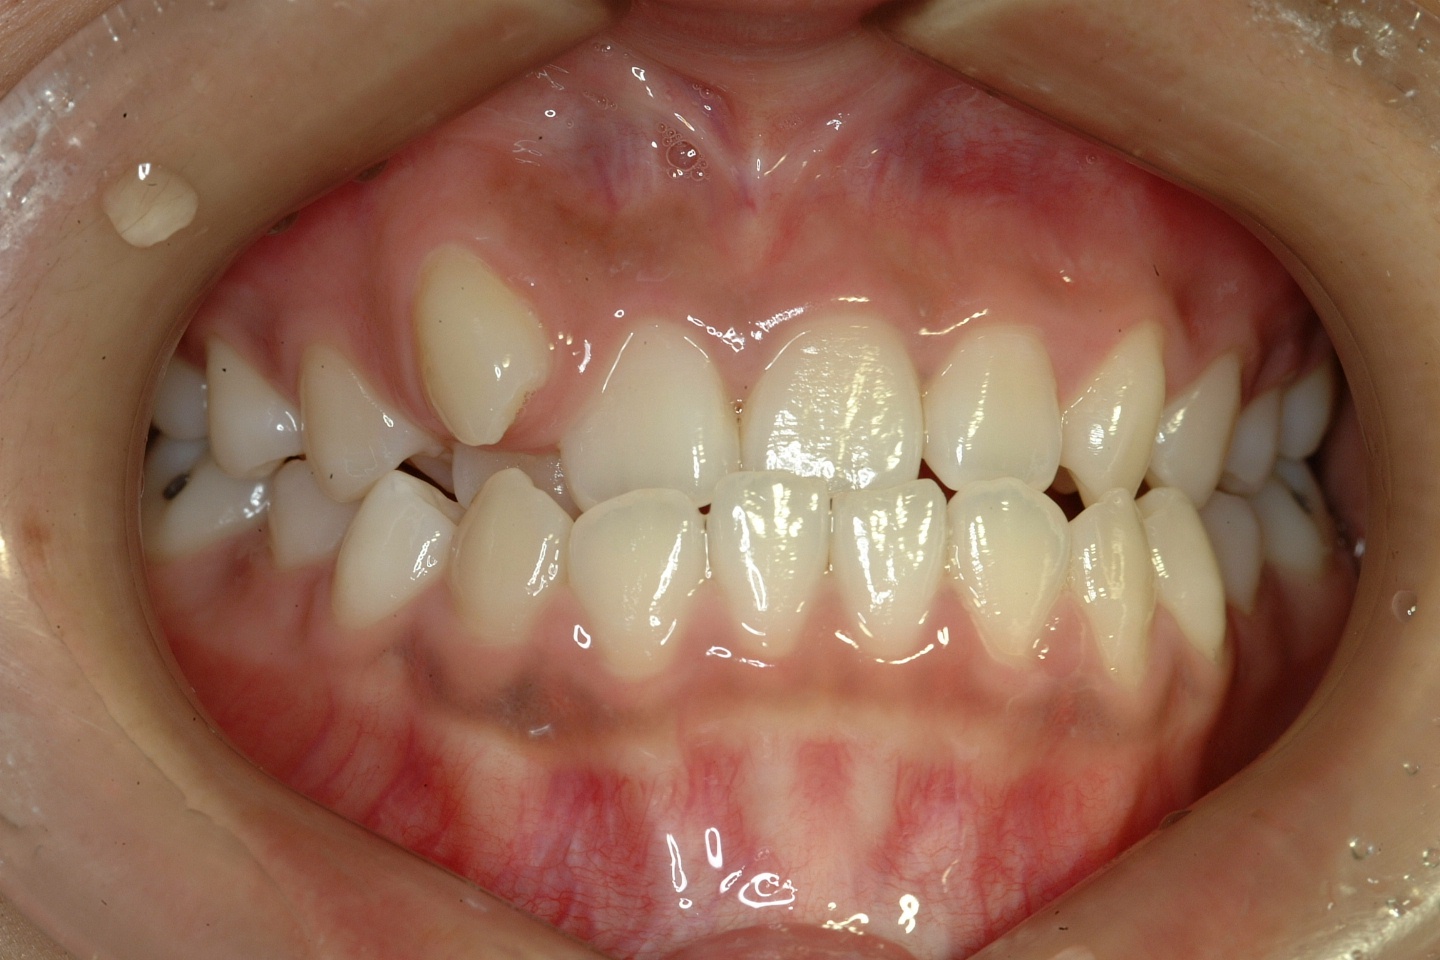

치료 전 사진입니다.